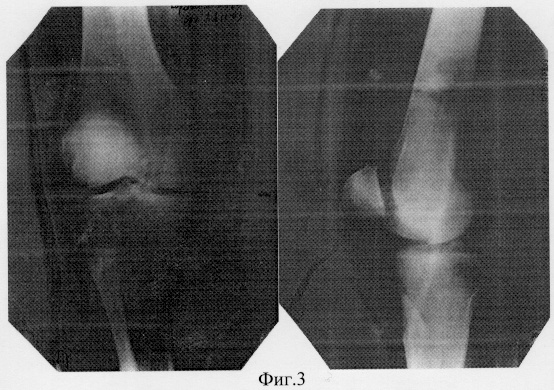

28.11.2003 года выполнена операция: реконструктивно-восстановительная с транспозицией участков мыщелков правой бедренной кости. Послеоперационный период протекал без осложнений (фиг.3 – состояние после операции).

11.12.2003 г. пациент выписан в удовлетворительном состоянии в гипсовом туторе. На контрольных рентгенограммах взаимосоотношения в правом коленном суставе правильные (фиг.4 – состояние после операции).